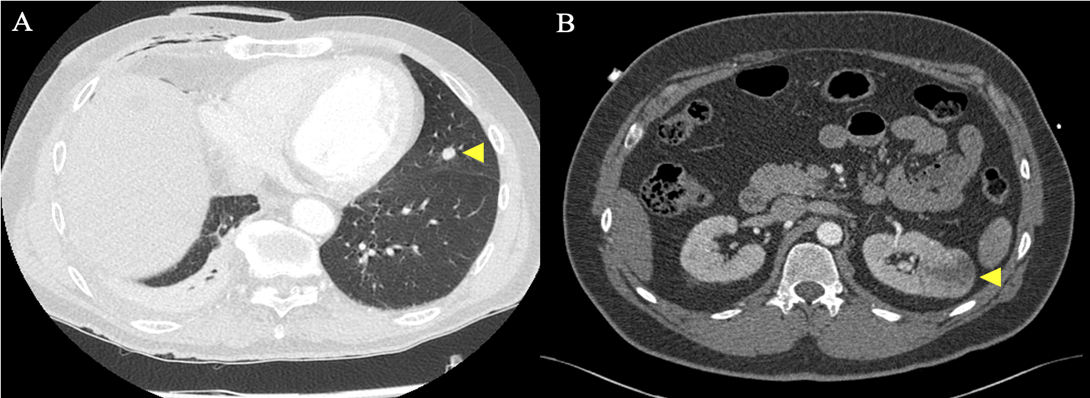

In total, 11 patients (13.9%) were excluded from MIMVS due to CT findings alone. CT exclusion criteria included: significant MAC (Figure 2A); significant coronary artery calcification (Figure 2B); dilatation of the ascending aorta to 4.4 cm (Figure 2C); significant mural thrombus in descending and abdominal aorta (Figure 2D); slender, calcified iliofemoral vessels (Figure 2E); dissection flap in the right external iliac artery (Figure 2F); incidental persistent left-sided superior vena cava (SVC) (Figure 2G); significant chest wall deformity (Figure 2H and 3A); incidental liver haemangioma (Figure 2I); 4.6 cm abdominal aortic aneurysm (AAA) (Figure 3B) and aberrant origin of the left circumflex artery (Figure 3C). A further 10 patients (12.7%) were excluded from MIMVS following multidisciplinary team (MDT) discussion due to: complexity of repair; non-isolated procedure and evidence of previous inferolateral myocardial infarction (MI). Additional CT findings resulting in modification of minimally invasive operative strategy included a partially bifid 4th rib (Figure 4A) and rib crowding (Figure 4B). Significant incidental findings that resulted in further investigation and referral to other pathways included a 10 mm lung nodule (Figure 5A) and 4 cm renal mass (Figure 5B).

Figure 5. Significant incidental findings resulting in further investigation and referral. Preoperative CT revealing: A) 10 mm nodule in left lung and B) 4 cm mass in left kidney.

Three-dimensional CT reconstructions of the thorax allow for assessment of chest wall anatomy and visualisation of the operating field in order to aid preoperative planning, reduce operative times and prevent potentially avoidable complications. Preoperative understanding of patient anatomy is particularly important in minimally invasive surgery as exposure is limited.2 In our experience, we have found that CT and 3D CT reconstructions are useful tools for accurately determining the optimal ICS for right-sided minithoracotomy incision based upon the position of the left atrium, pulmonary vessels and right hemi-diaphragm. The fourth ICS is the optimal incision point in 65.8% of patients (Table 2). We also use CT and 3D CT reconstructions to assess chest wall deformity. Significant chest wall deformity may be a contraindication for MIMVS depending upon the surgeon’s experience. One patient was considered unsuitable for MIMVS due to significant pectus excavatum (Figures 2H and 3A) that may have caused difficulty with surgical approach. Other patients required modification of minimally invasive operative strategy due to rib crowding (Figure 4A) and a partially bifid 4th rib (Figure 4B). CT and 3D CT reconstructions are also used to visualise aberrant vessel anatomy (Figure 3C) and subjectively assess iliofemoral tortuosity in order to aid preoperative procedural planning and prevent potentially avoidable complications.2 Additionally, preoperative CT may highlight incidental extra-cardiac findings that may exclude the patient from MIMVS (Figure 2I) or require further investigation and referral to additional pathways (Figures 5A and 5B).